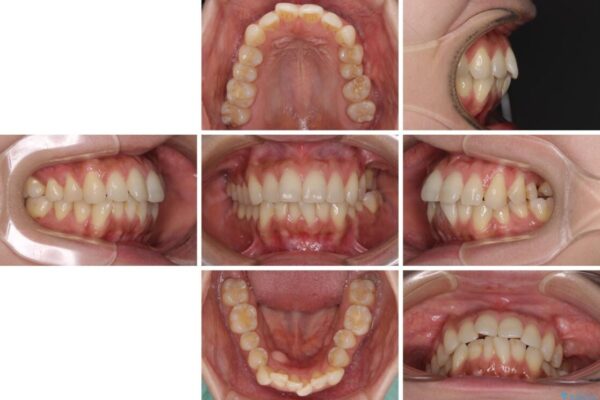

治療途中

• インビザラインによる矯正治療と奥歯のインプラント治療 治療途中画像